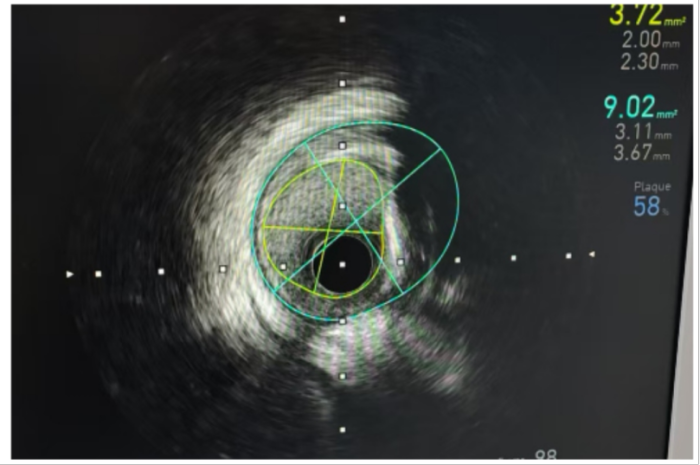

IVUS(血管内超声)可以被视为透视冠状动脉的“第三只眼睛”,IVUS作为一种先进的冠状动脉腔内影像技术,使用安装在心导管顶端的微型超声探头,实时显示血管的截面图像,以极高的分辨率展示血管壁的细节:如血管管壁结构的厚度、管腔大小和形状等,精确地测量血管腔径及截面积,甚至可以辨认钙化、纤维化和脂质池等病变的大小和程度,发现冠脉造影不能显示的血管早期病变。基于这些信息,医生可以更准确地选择冠脉植入支架的尺寸、类型,以及确定最佳植入位置,大大降低手术风险。

8月15日,心血管内科执行副主任涂涛与行政副主任蒋小菊带领心血管团队在IVUS指导下顺利完成患者右冠脉和回旋支病变的介入治疗。术后再次使用IVUS进行检查,证实支架贴壁良好,无残余狭窄,患者的冠脉血供得到了显著改善。患者对手术过程的体验感及效果给予了充分的肯定和高度评价。

术中IVUS显影